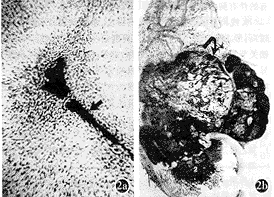

图2 a) 软骨肉瘤切片(HE染色)显示瘤软骨细胞以血管(箭头)为中心生长。b) 股骨下端骨肉瘤病理大切片(HE染色)显示肿瘤内有三种组织成分。包括肿瘤骨(1),瘤纤维(2),瘤软骨(3),注意瘤软骨占主要成分,呈分叶状生长(弯黑箭)瘤软骨以血管(黑箭头)为中心生长。